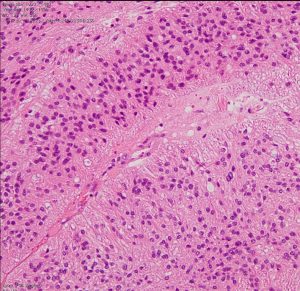

第4脳室床に発生した典型的な上衣腫 EPN-PFA の画像です。水頭症になって,頭痛と嘔吐,意識障害で発症しました。典型的なMRI画像と病理所見です。MRIでは第4脳室からマジャンディー孔を越えて脊髄背側まで長く腫瘍が伸びています。腫瘍内部に小さなのう胞が複数みられます。病理像では,血管周囲に細胞核がない無核野が認められます。血管周囲に伸びた繊細な単極性突起が集まった領域です。これは,血管周囲偽ロゼット perivascular pseudorosette という上衣腫に特徴的な病理所見です。

摘出した標本のHE染色です。左側ではperivascular pseudorosette(血管周囲の無核野)がみられ,右側ではependymal tube (ependymal canal) が認められます。

左がGFAP染色、右がMIB-1(Ki-67)染色です。 GFAPは腫瘍血管の周囲の無核野に強陽性です。MIB-1 labelling index が1%以下であり,この上衣腫の増殖能が極めて低いことを示しています。このような高分化型で増殖能の低い上衣腫は脊髄髄内には多いのですが,脳では珍しいものです。ovex中心上衣腫にみられます。

組織像はグレード2,小型円形の均一な核をもち血管周囲には無核帯所見があります。EMA epitherial membrane antigenは陽性です。MIB-1染色率は非常に高く15%くらいが陽性で,再発の可能性を予想させるものでした。

グレード2の組織像です。血管周囲に無核野があり,腫瘍の核は血管から離れているパターンが特長です。perivascular pseudo-rosetteといいます。